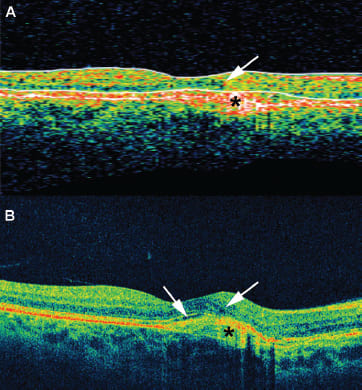

Figure 1 shows a comparison between the higher-resolution Cirrus scan and the corresponding Stratus scan taken from the same patient on the same day. Most graders would not recognize the presence of fluid on the Stratus scan; however, the Cirrus scan shows trace amounts of intraretinal and subretinal fluid. Figure 2 shows an example in which the typical clinical interpretation would miss the intraretinal fluid unless a more careful review of the raster or macular cube scans was performed. Reading center graders systematically review macular cube scans, whereas clinicians often do not.

Figure 1. Comparison of time-domain OCT with spectral-domain OCT. Scans taken from the same patient on the same day demonstrate the increased resolution from the spectral-domain OCT (Cirrus) compared with the time-domain OCT (Stratus). On the Stratus (A), there is a questionable area of intraretinal fluid that blends in with the background noise, whereas on the Cirrus (B), there is more definitive intraretinal and subretinal fluid. The white arrows denote the areas of fluid, and the black asterisks denote the choroidal neovascular membrane.